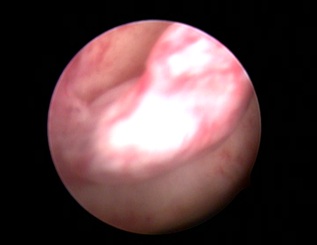

Hysteroscopy showing Polyp in Uterine Cavity.

Three-Dimensional Ultrasonography (3D USG) in comparison to hysteroscopy is less invasive, cheaper, easily accepted by most patients and does not require much training. In most cases an endometrial polyp can be differentiated from the submucous fibroid based on the imaging characteristics. The polyps are typically round in shape, smooth in outline, and are generally echogenic, compared to the endometrium or are isoechoic to it. The underlying endometrial-myometrial interface is preserved (Figure 5). Moreover the presence of a vascular pedicle has a positive predictive value of up to 81.3%. Fibroids are more inhomogeneous, hypoechoic, and there is a loss of endometrial-myometrial interface. The percentage of the intra cavitary portions of the submucous fibroids i.e., grade of submucous myoma can be assessed on 3D USG by the degree of distortion caused by it (Picture 6).